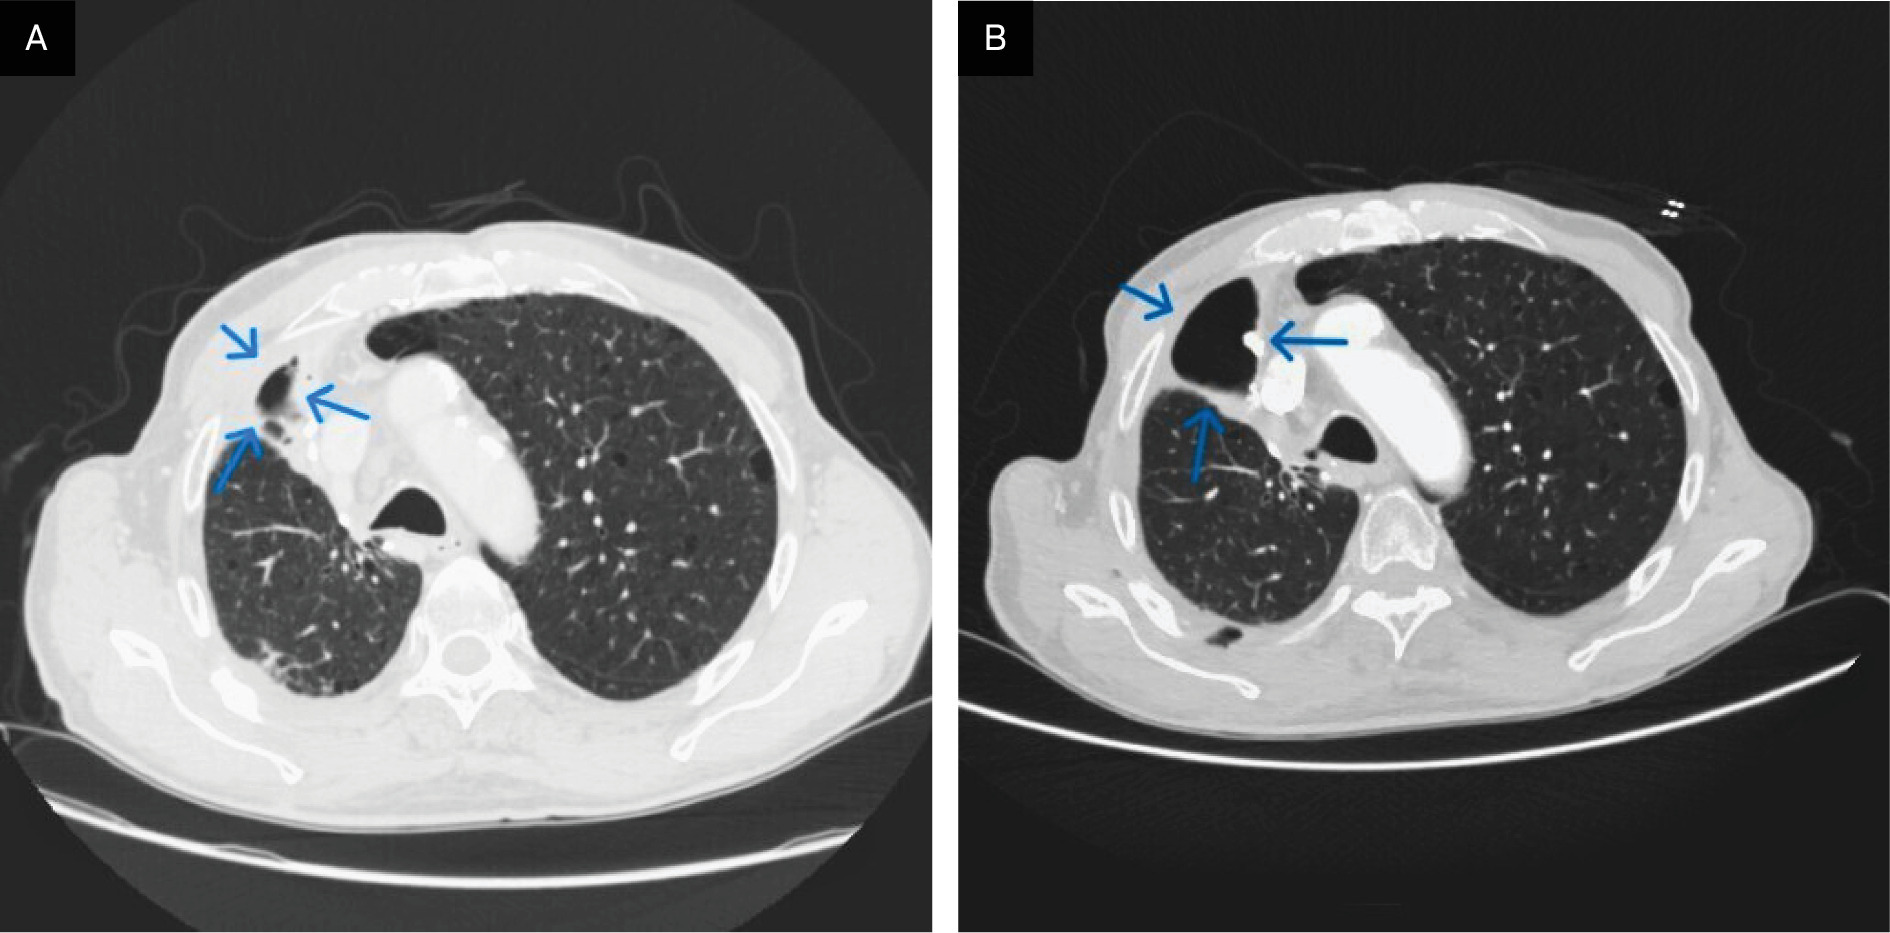

Postoperative thoracic CT (Figure 3A and B) revealed a loculated right-sided hydropneumothorax and confirmed the outcomes of right upper lobectomy with resection of the lateral arches of the second and third ribs. A thin residual pleural effusion and minor subpleural consolidation were present. Paraseptal emphysema persisted in the left upper lobe. Enlarged paratracheal mediastinal lymph nodes, measuring up to 2 cm, were subsequently evaluated histologically by endobronchial US-guided biopsy.